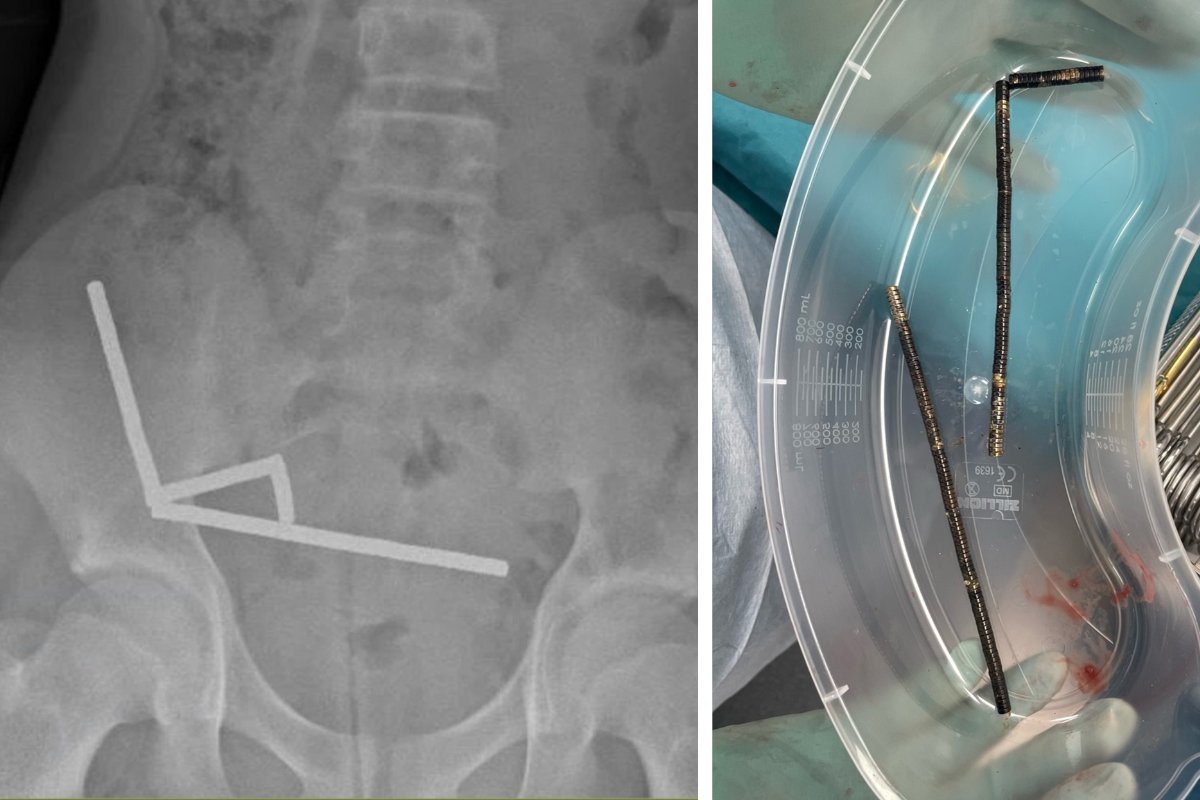

Galéria k článku Chlapec (13) mal neznesiteľné bolesti: Zjedol takmer STO magnetov! Prišiel o kus čreva

Zdroj: New Zealand Medical Journal